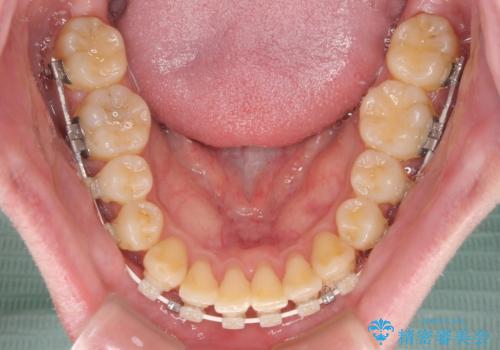

- 矯正装置

- 審美装置

- 治療期間

- 1年1ヶ月

インビザラインでもワイヤー装置でも矯正治療は可能でしたが、煩わしい自己管理なしに短期間で治療を行いたいとのことで、目立たないワイヤー装置にて治療を行うこととしました。